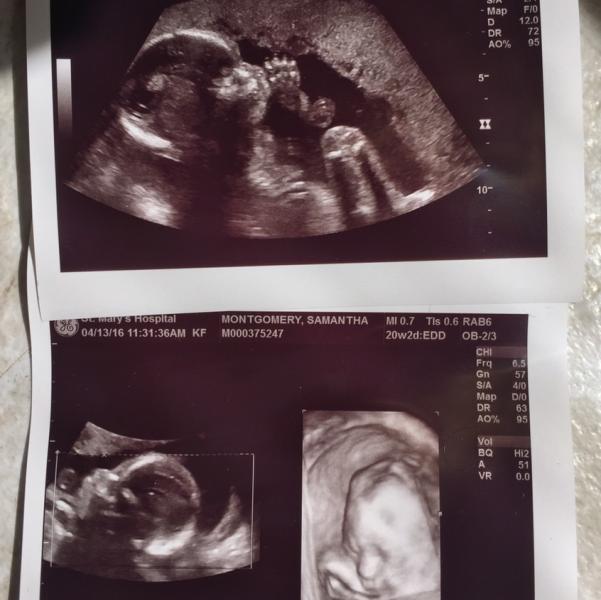

oooooook. I need some support or words of encouragement. I recently had my midway ultrasound at 19 weeks (last week). My doctor's office called me and told me that they didn't get good enough views of the spine and needed to schedule another one..I was like, ok..but everything is fine? And the woman said "Oh yes!" Then, a few days later, the midwife from my doctor's office called & told me that they saw something called an "echogenic intracardiac focus" in my baby's heart...which is essentially a white dot in the picture. It is associated with a small percent increased risk of chromosomal abnormalities like Down's Syndrome. Hearing all of these words FREAKED ME THE F OUT. My bf and I cried..we went in and tried to get a better understanding, and the midwife was like "No! Your baby is 99% perfectly healthy we just want to do blood test to be SURE." So I got the maternity 21 blood test and another ultrasounds today. Now we wait. The more I look online, the better I feel, but it's still really scary. Has anyone else gone through this?

On a positive note, the girl who did our ultrasound today was soooo nice and even switched on the 3D which she isn't supposed to do lol. Our baby boy was sucking his thumb! But, the white dot was still there. (Which is to be expected). Supposedly they mostly disappear on their own during the third trimester.